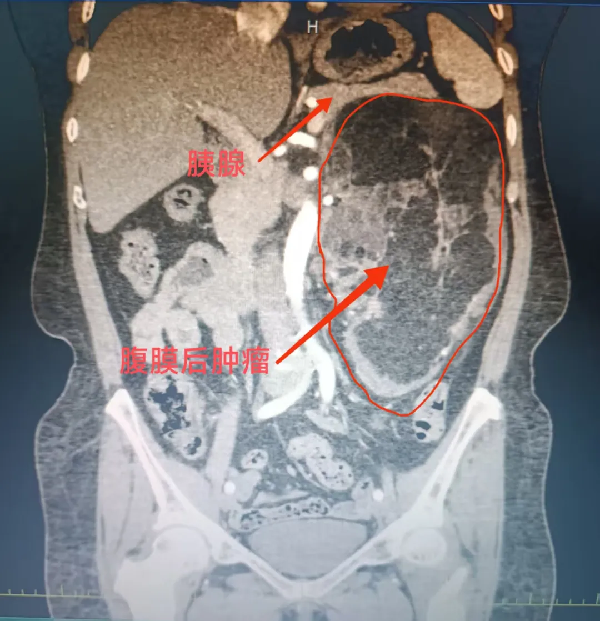

1个月前,闫女士在当地医院体检时,意外发现腹膜后藏着一枚巨大肿瘤。进一步检查显示,这枚肿瘤不仅体积较大,像藤蔓”一样紧紧缠绕着胰腺、左肾及肾血管——这些都是人体腹部的“关键命脉”,稍有不慎就可能引发大出血,甚至危及生命。

“肿瘤位置深、体积大,还与重要脏器血管紧密粘连,单纯靠一个科室很难完成手术。”杨庆强仔细研读影像资料后,精准判断出手术的核心难点。这枚肿瘤不仅尺寸较大,还将左肾推挤移位,与肾血管、胰腺的边界模糊不清,任何操作失误都可能导致难以控制的血管损伤。